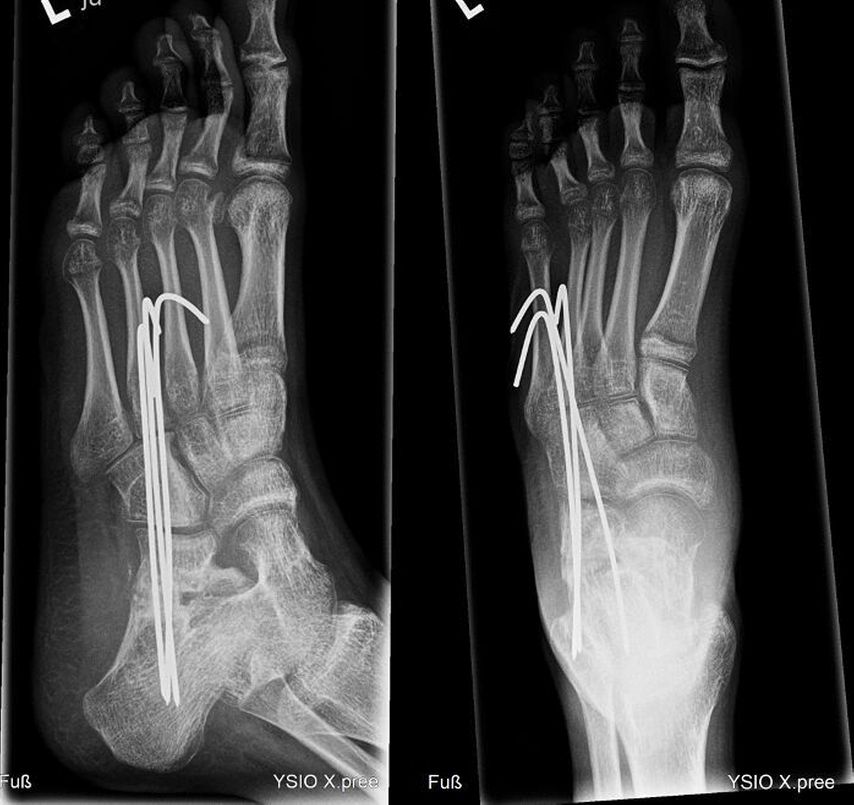

Bei einem 9-jährigen Mädchen mit angeborenem Knick-Senk-Fuß beidseits wurde ein kommerziell verfügbarer Allograft-Knochenblock zur Evans-Osteotomie erfolgreich angewendet. Im Rahmen einer ersten Operation wurde der rechte Fuß adressiert (Abb. 1) und im Verlauf ein Jahr später das gleiche Verfahren auf der Gegenseite problemlos eingesetzt. In der Verlaufskontrolle 1 Jahr postoperativ zeigen sich eine gute knöcherne Einheilung, eine adäquate Fußaufrichtung und eine Verlängerung der lateralen Säule. Das Allograft ist nativradiologisch noch abgrenzbar. Ein weiterer Fall einer komplikationslosen Evans-Osteotomie mit kommerziellem Allograft-Knochenblock ist der eines 14-jährigen Jungen mit Knick-Senk-Fuß links. Abgebildet ist die Verlaufskontrolle 6 Wochen postoperativ, wobei im Rahmen der ambulanten Kontrolle die Kirschnerdrähte nach 6 Wochen entfernt wurden. Ein Folgeröntgen ist noch ausständig (Abb. 2). Bei einer 15-jährigen Patientin mit schmerzhaftem Knick-Senk-Fuß beidseits zeigt sich ebenso eine adäquate Fußkorrektur in der Jahreskontrolle nach Evans-Osteotomie mit Allograft-Knochenblock rechts. Eine Versorgung der Gegenseite ist geplant (Abb. 3). Auch im Fall eines 11-Jährigen mit Serpentinenfüßen kamen bereits Allograft-Knochenblöcke erfolgreich zum Einsatz: Präoperativ zeigte sich hier ein Rückfußvalgus mit Vorfuß adductus und damit verkürzter lateraler Fußsäule. Als operative Sanierung wurde eine Fußkorrektur durchgeführt, die Aspekte einer modifizierten Cotton-, Evans- und Cuboid-Osteotomie enthält. In der postoperativen Röntgenaufnahme 8 Wochen später zeigte sich eine gute knöcherne Einheilung bei stabiler Korrektur, sodass die Drähte gezogen werden konnten (Abb. 4).

Abb. 1: 9-jähriges Mädchen mit Knick-Senk-Fuß, prä- und postoperative Röntgenaufnahmen des rechten Fußes, vor und nach Evans-Osteotomie. Postoperativ zeigt sich eine adäquate Fußaufrichtung und Verlängerung der lateralen Säule